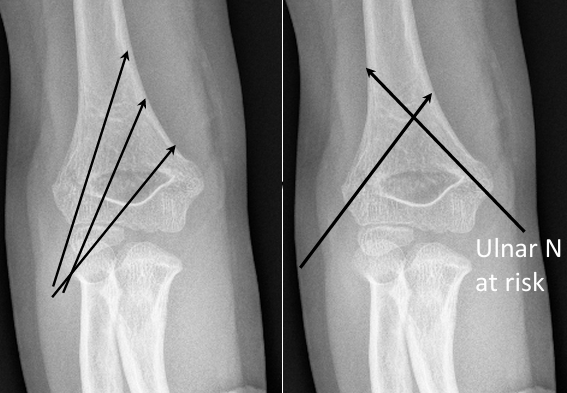

• 核心风险:交叉克氏针中的“内侧针” 。 -

• 机制: 传统上为了追求最强的稳定性,我们使用交叉针固定。但在肘关节极度屈曲时,尺神经会大概率向前“半脱位”,滑到内上髁的前方,正好跑到我们内侧针的进针轨道上。 -

• 后果: 导致术后出现新的尺神经麻痹症状。 -

1. 预防为王: 预防医源性损伤是重中之重。Gartland III型骨折,如果交叉针把握不大,优先使用“外侧三针”,或者在伸肘位(<90度)+ 小切口下置入内侧针,这样操作可以让尺神经“滑动”回尺神经沟内,离开内侧针的“进针路径”。这样可几乎完全避免尺神经损伤。 -